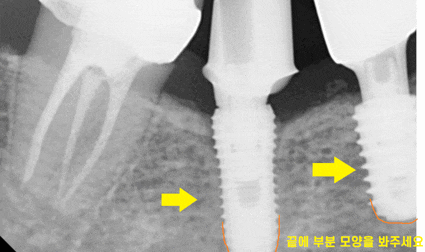

x-ray를 찍어보았습니다.

임플란트는 잘 남아있고

머리부분인 보철이 없어졌네요.

보시면 양쪽 임플란트 모양이 다르게 생겼죠?

다른 회사 제품이라는 뜻입니다.

임플란트 만드는 회사마다 디자인도 규격도 다 다릅니다~!

뿌리 끝 다른거 보이시죠?